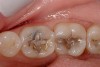

Figure 6